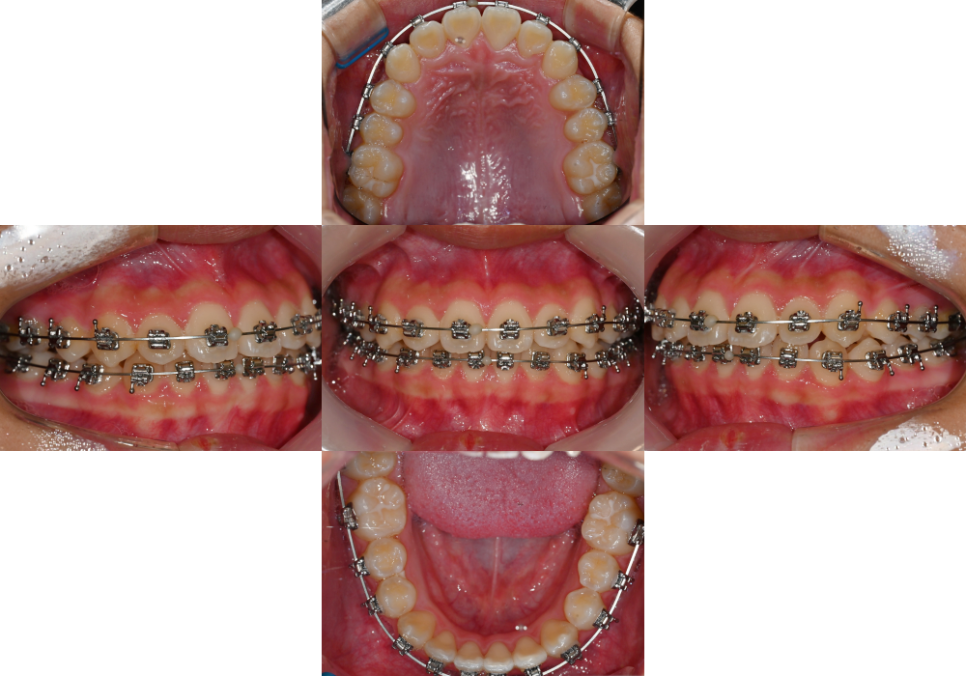

| 4. 교정 치료 후 어떤 변화가 있을까요?

2025.01.24

치열이 개선되면

여러 가지 긍정적인 변화를

경험할 수 있습니다.

우선 구강 위생 관리가 훨씬 쉬워집니다.

엇갈려 있던 치열이 펴지면서

칫솔질이 자연스럽게 편해지고,

음식 찌꺼기가 끼는 일도

줄어들게 되는데요.

이는 충치나 치주 질환의 확률을

크게 줄여주는 효과를 가져다 줍니다.

또한 턱관절의 통증을 줄여주거나

안면 비대칭을 개선하는 등

배열 개선 외에도 여러 문제들을

해결할 수 있는 치료 방법이랍니다.

치료기간 : 23.08.17 ~2025.01.24